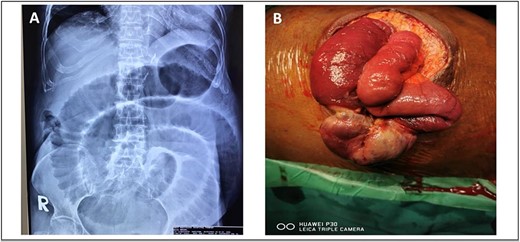

He presented with a history of abdominal distension for 1 week, loose stool, and vomiting for 3 days. Since admission to the ward, he had no bowel opening and did not pass flatus. On examination, he appeared dehydrated, and his abdomen was soft but distended. Plain abdominal radiograph showed dilated bowel. Computed tomography of the abdomen and pelvis showed short segment thickening of proximal transverse colon with dilatation bowel proximally, enlargement of mesenteric nodes, and mild ascites (Fig. 1). We proceeded with exploratory laparotomy, right hemicolectomy, and double barrel stoma. Intraoperatively, a noted tumour at proximal transverse colon size of about 5 × 4 cm with proximal bowel dilatation and distally bowel collapsed. Multiple mesocolic nodes were also present.

(A) Axial view and (B) coronal view of computed tomography showed short segment thickening of proximal transverse colon (red arrow) with dilatation of bowel.